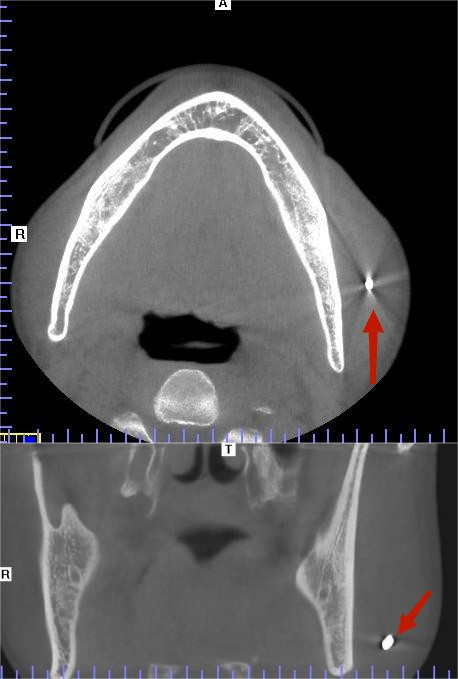

8月3日,刘先生来到捷克论坛 马王堆院区口腔二病区就诊,接诊的余顺主治医师查看伤势后发现,金属碎片进入的左侧面部皮肤仅一个接近闭合的小孔,完全判断不出异物进入的方向和位置,这给异物取出带来了难度。同时,颌面部不仅血管神经非常丰富,还关乎脸部外观,余顺医生决定为其进行微创手术。

在超声科隆雯静主治医师的超声精确定位引导下,手术在门诊局麻下进行,切口不超过1cm,仅伸入一把手术血管钳,小心探查到异物位置,顺利钳夹取出,手术时间仅十余分钟,术后抗感染治疗,创口恢复很好,刘先生对医生们表示感谢。

口腔科张特主任表示,口腔颌面部因特殊的解剖结构及位置,较容易受到外伤造成异物残留,异物原则上应尽量手术取出。口腔颌面部神经血管丰富,解剖结构复杂,以及残留异物的种类、数量、大小和位置具有多样性,使异物精确定位和取出的难度和风险增大。传统手术方法通过术前影像学检查对异物定位后进行手术取出异物,无法实时地反映术中异物与周围解剖结构的空间关系。通过术中超声科精准定位,能动态了解手术器械与异物的相对位置,指导异物取出,为患者提供更加优质的医疗技术。(口腔二科  余顺)